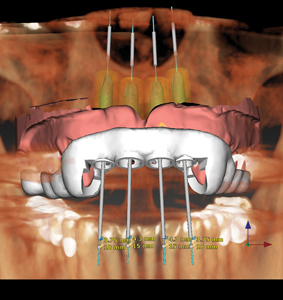

The following case presentation will illustrate an anterior maxillary reconstruction with the use of dental implants and fixed prosthodontics. Our patient (P.C.) presented to the office with the pre-existing dental treatment done over 10 years ago as illustrated in Figures 1 and 2. Due to a large diastema between 11 and 21, the previous practitioner … Read more